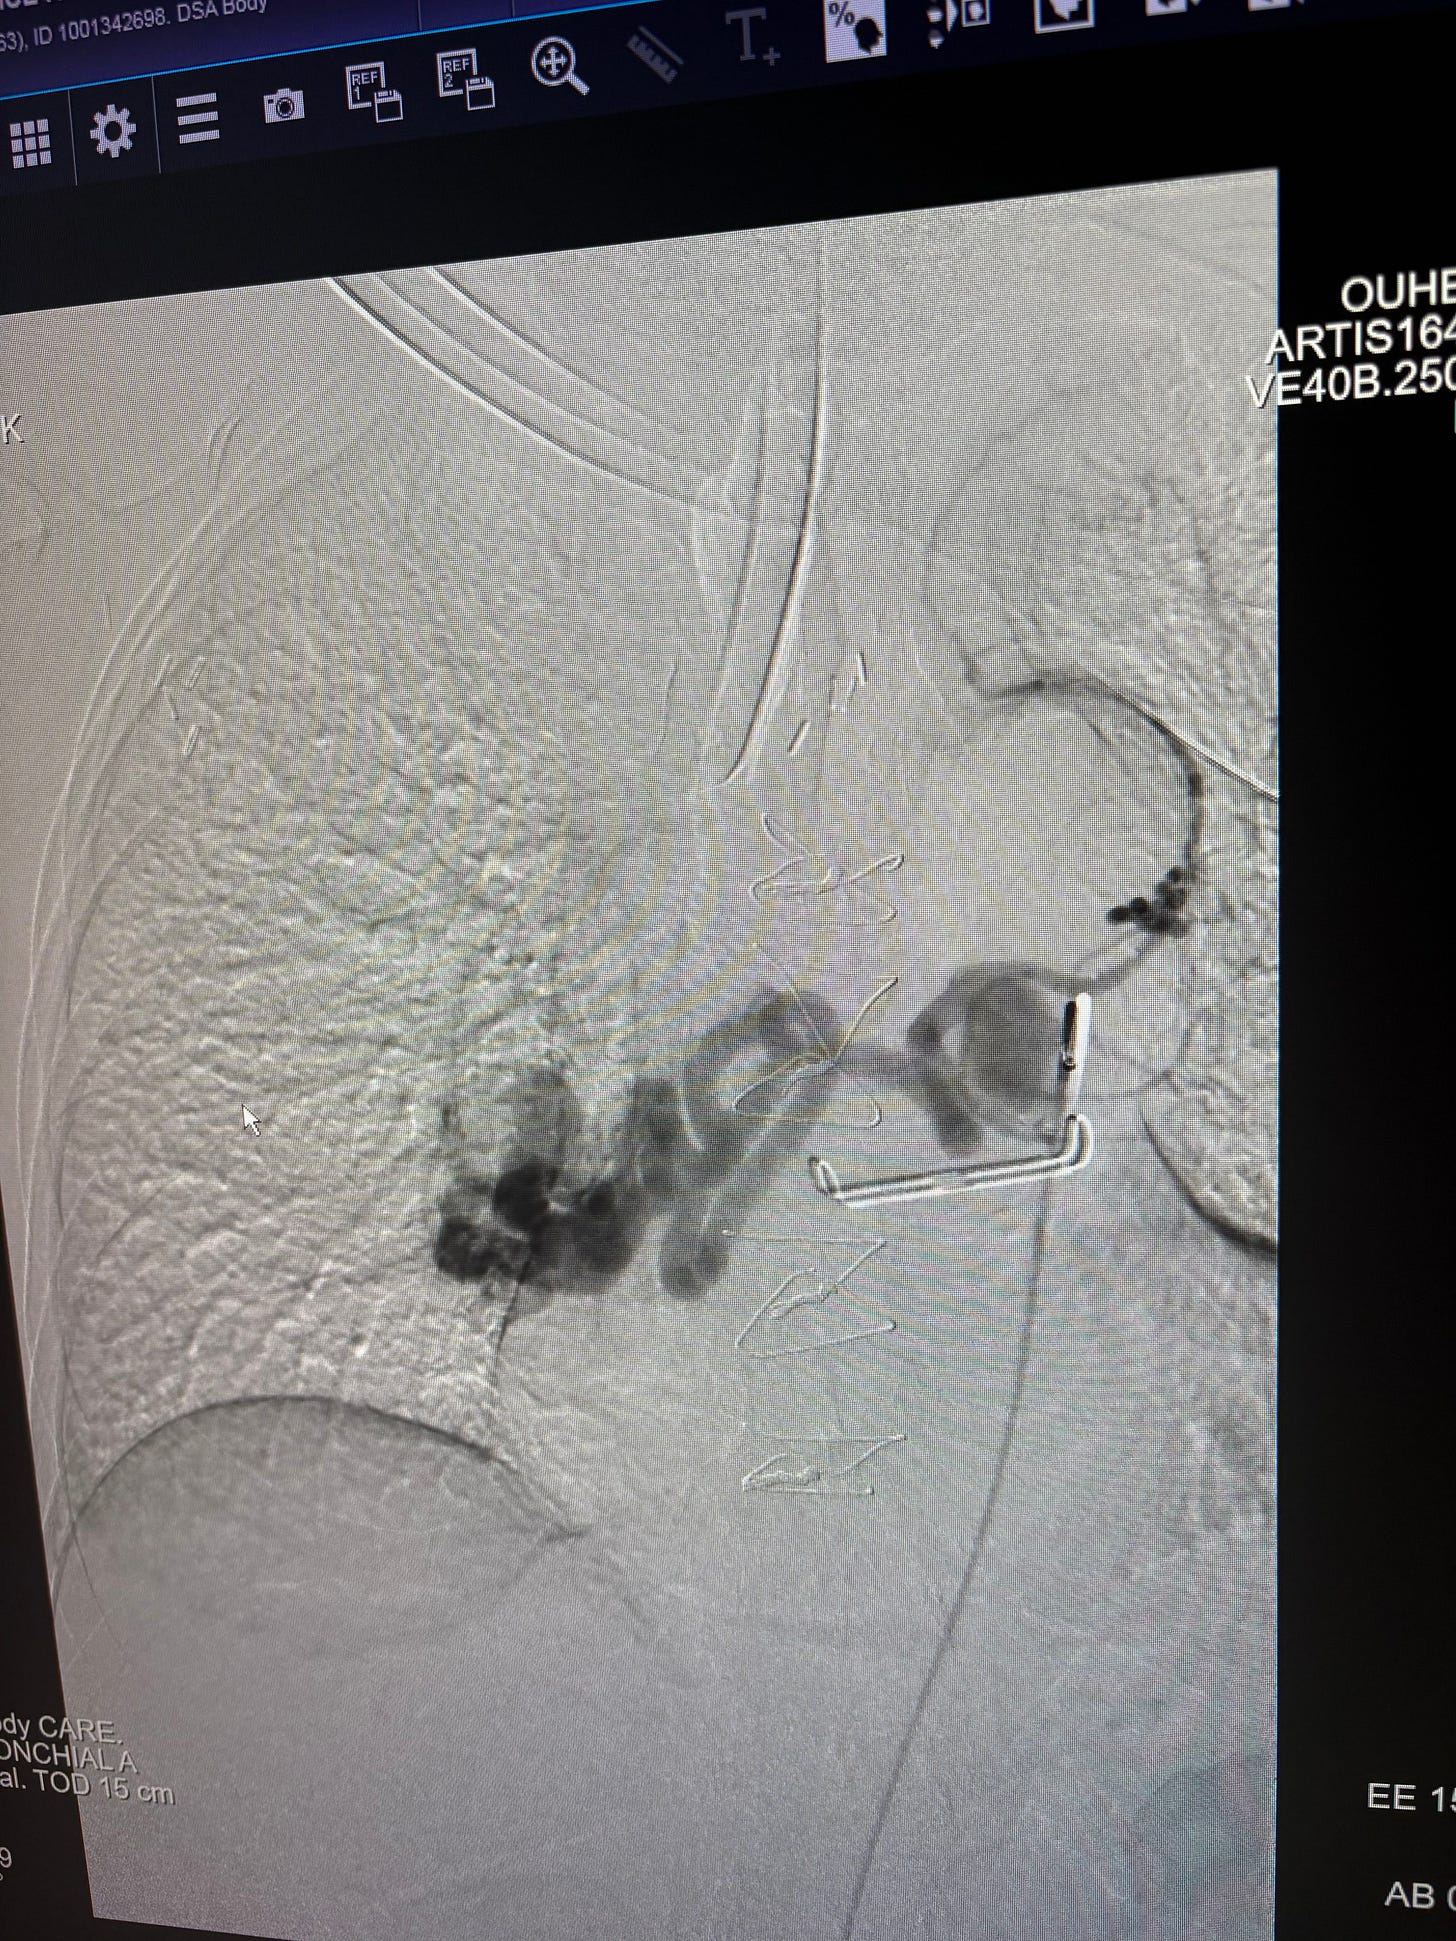

Now for the potentially boring part. Below are before and after images of my bronchial artery aneurysm and bronchial artery aneurysm to pulmonary artery fistula. As I probably mentioned on here before, each is rare, but to have them both together is “exceedingly rare.” Here’s the not boring, praise-the-Lord part: Prior to the procedure, the interventional radiologist planned to embolize the fistula as deeply as possible then see how I did and do the larger aneurysm later. But he was very happy he was able to fill nearly the whole squiggly, aneurysmal artery plus the bigger bulging artery. I now have 23 platinum coils in there. When I texted my oldest that information, he texted back, “Platinum is $2,000/oz now. Looks like me and Cam (sister) will be taking you to the pawn shop pretty soon.” So funny.